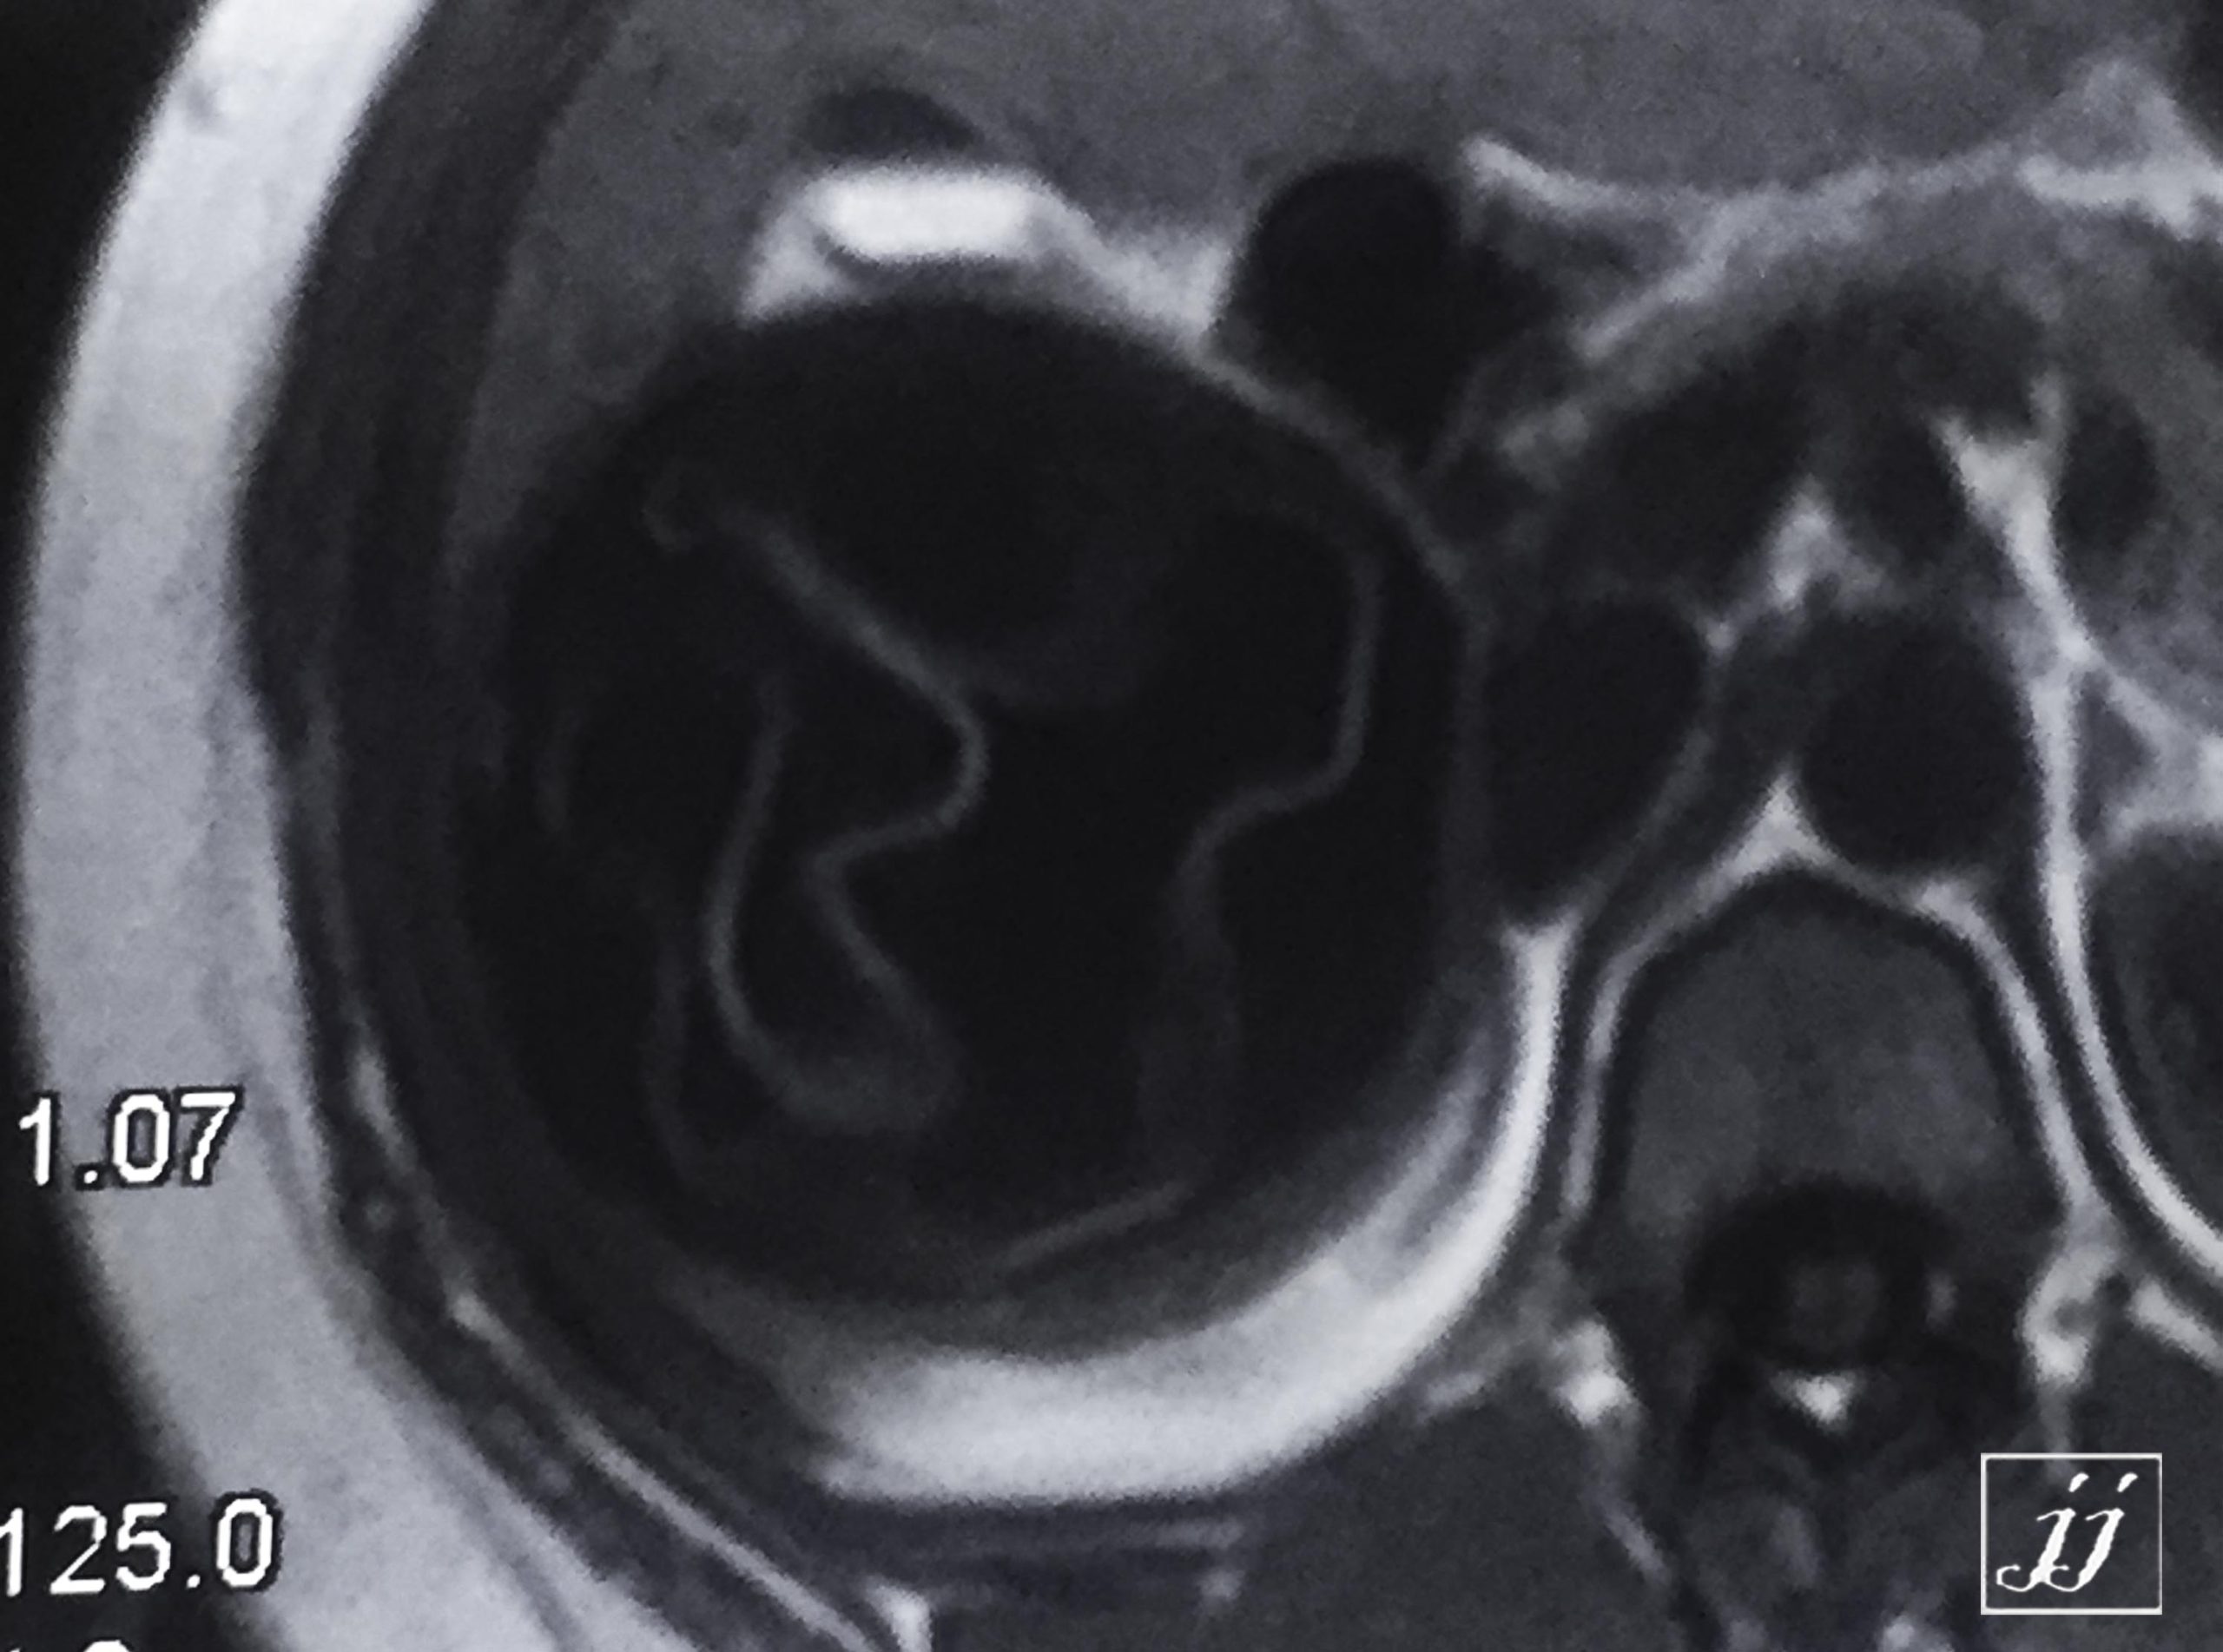

Abdomen- liver hydatid cyst, dead mother alive daughter (4)